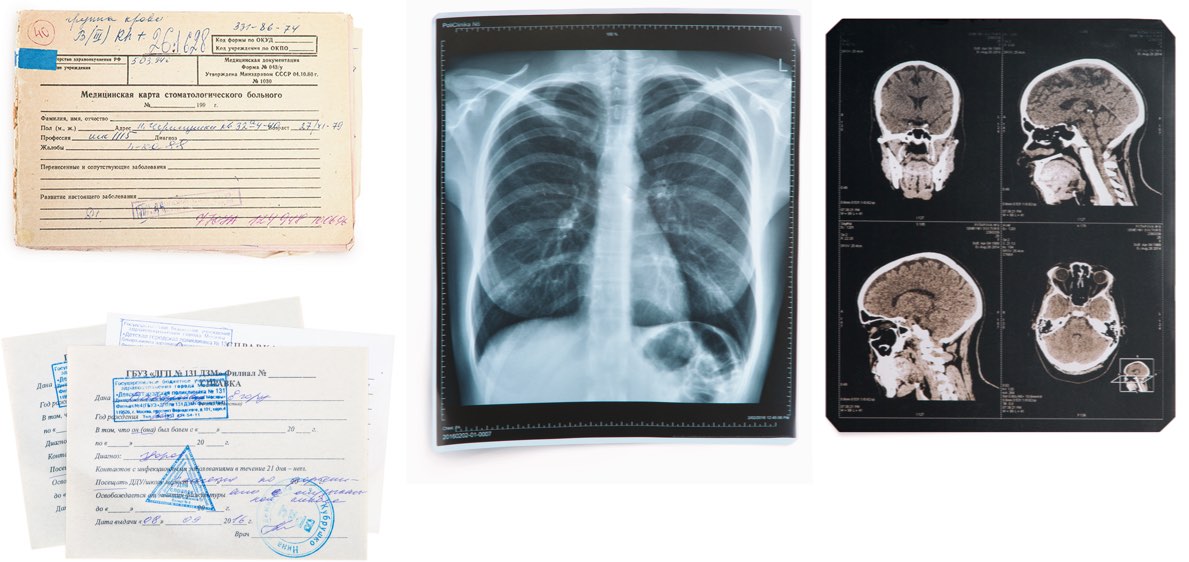

Finding medical objects, test results, a medical log book and doctor notes to illustrate the health test.